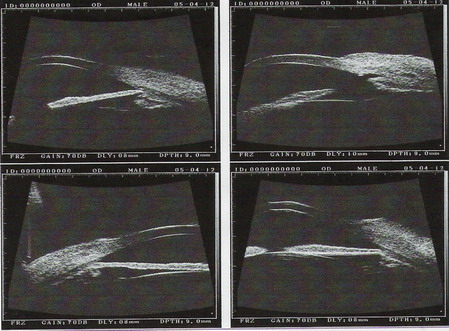

2005年4月12日右眼UBM图像